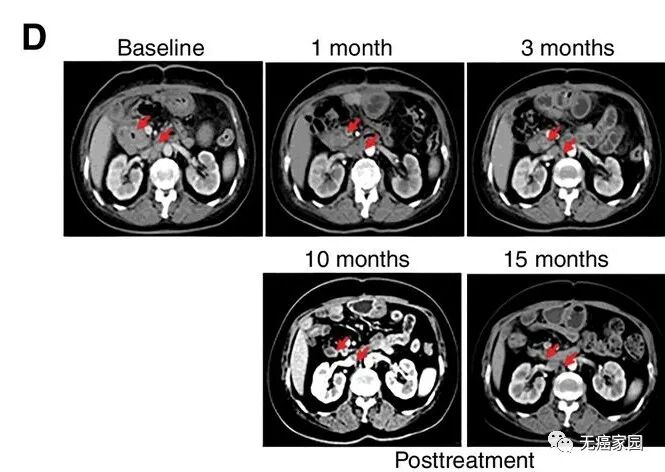

研究结果显示,17例患者可评估,其中1例胆管癌患者的肿瘤完全消失,截止到目前疗效已经保持了22个月,尚未发现疾病复发。10例患者疾病稳定,疗效保持2.5~15.5个月,中位无进展生存期为4个月。

图片

CART-RGFR细胞治疗之前和1、3、10和15个月患者1的CT扫描图像。

红色箭头表示原发肿瘤和腹膜后淋巴结转移。